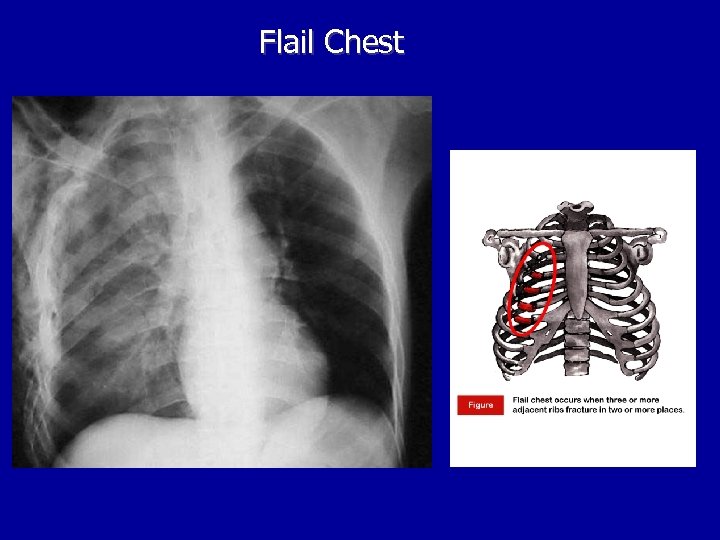

Other Laboratory Findings in ARF CXR Abnormalities Complete Blood Count (look at WBC and Hgb, which may suggest chronic hypoxia) Electrolyte Abnormalities (look at bicarbonate)

Flail Chest